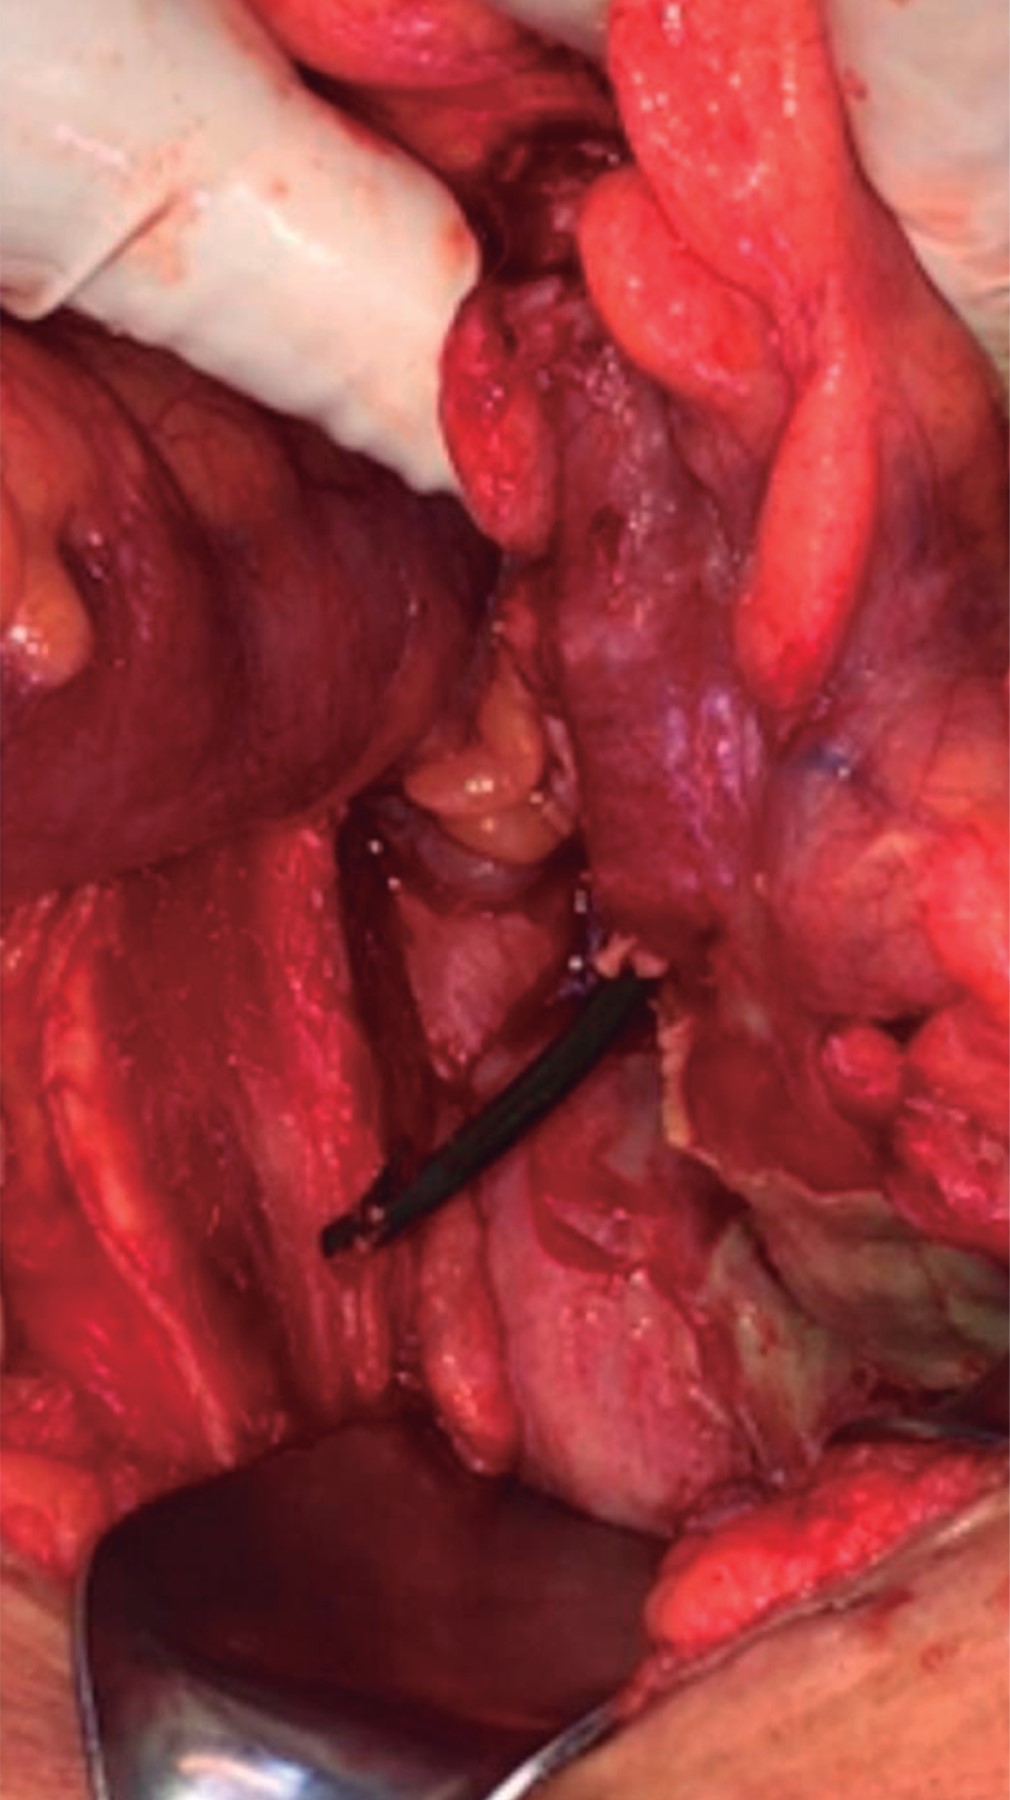

The patient underwent exploratory laparotomy, where a one-centimeter diameter perforation was found through a sigmoid colon diverticulum secondary to the stent (Figure 3) and multiple uncomplicated sigmoid diverticula. The stent was removed, the intestinal edges were debrided of healthy tissue, and primary closure was performed in two planes, the internal by continuous suture with 3-0 caliber polyglactin 910 and the external through Lembert type stitches with 3-0 caliber silk. There was no evidence of localized or generalized peritonitis, but in any case, a 12 Fr caliber closed suction drain was placed, directed to the parietocolic slide and pelvis. Postoperative evolution was uneventful; ceftriaxone 2 mg every 24 hours intravenously and metronidazole 500 mg every eight hours were administered; the patient was discharged on the fourth postoperative day, with an indication to complete five more days of metronidazole 500 mg every eight hours orally.

Figure 3